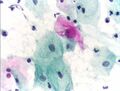

- آفة حرشفية عالية الدرجة داخل الظهارة (HGSIL أو HSIL)

![]() آفة حرشفية عالية الدرجة داخل الظهارة. | |